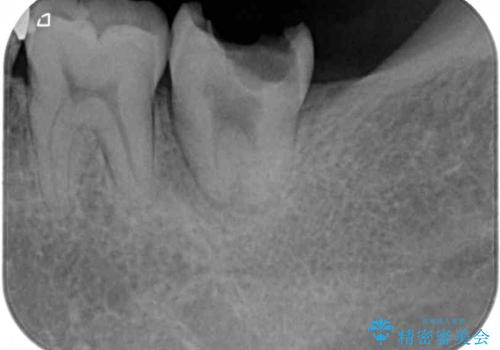

- 下顎奥歯のむし歯治療を希望して来院された患者様です。

対合の上顎の奥歯は、むし歯で欠損した部分と咬み合うように伸び出してきていました。

下顎のむし歯の範囲が広く、既に神経は失活しており、根管治療が必要な状態でした。